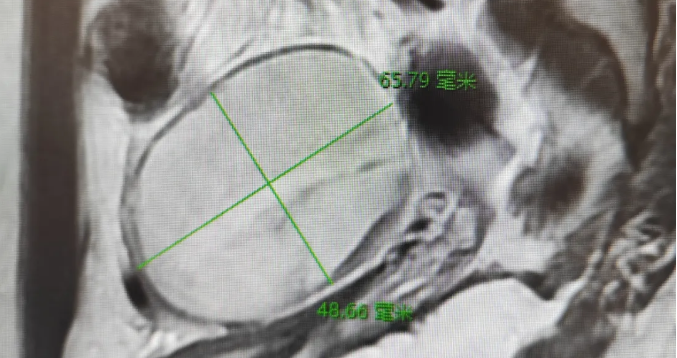

成功剔除卵巢囊肿,保留了卵巢功能,避免对患儿生育功能造成影响。腹部伤口隐蔽,满足了患儿及家属对美观的需求。